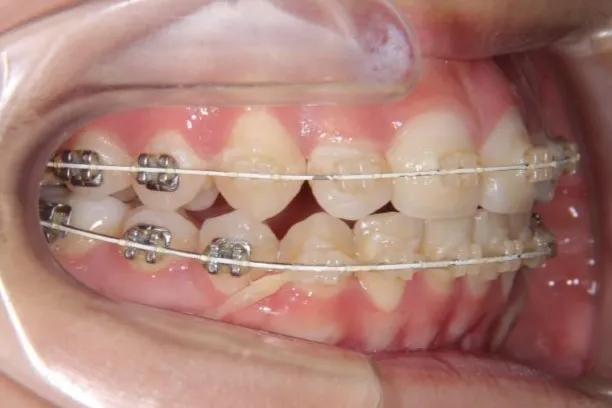

• 初診

治療経過1